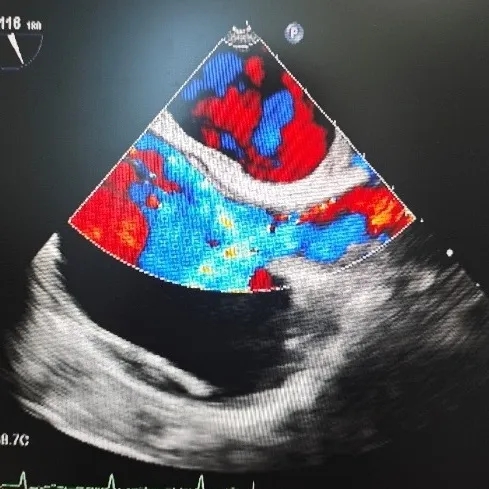

超声所见:右心声学造影:两支10ml注射器,分别抽取1ml空气和8ml生理盐水,经三通管相连,回抽1ml静脉血,使三者在2支注射器间反复推注10次以上,充分混合后置于1支注射器内,将配置好的造影剂快速经右肘正中静脉推注后,右房、右室即刻微泡显影,左房、左室未见显影,嘱患者经瓦氏动作,左房、左室仍未见微泡影。

超声结论:右心声学造影:阴性(无右向左分流)。